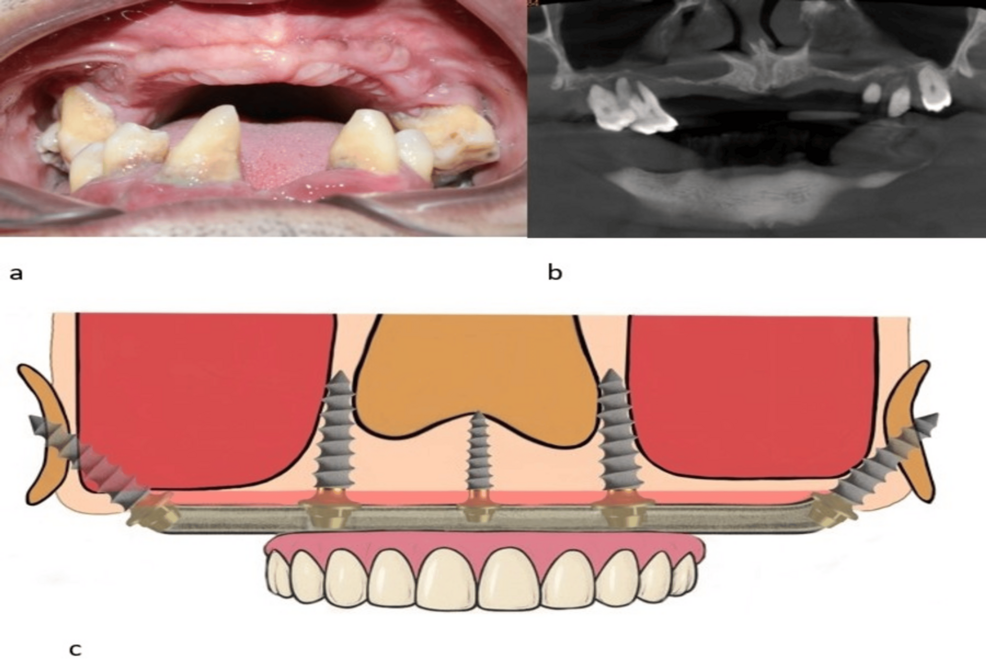

„Implanturi fără adiție osoasă –Dacă vi s-a spus că aveți o resorbție osoasă severă și că singura soluție este adiția de os – un proces lung și costisitor – implantologia bicorticală reprezintă alternativa modernă pe care o căutați. Această tehnică avansată utilizează partea cea mai densă și stabilă a osului (corticala), permițând fixarea implanturilor chiar și în cazurile cu atrofie maxilară accentuată.

De ce să alegi implantologia bicorticală ?

Spre deosebire de metodele tradiționale care necesită luni de vindecare, sistemul bicortical -Dinți ficși fără adiție osoasă

este conceput pentru încărcare imediată. Asta înseamnă că vă puteți recăpăta funcția masticatorie și estetica zâmbetului în doar câteva zile.

Fără adiție de os: Eliminăm necesitatea procedurilor invazive de augmentare osoasă sau sinus lift.

Stabilitate excepțională: Fixarea în osul cortical garantează o ancorare mult mai puternică încă din prima zi de la implantare.

Fiecare plan de tratament este personalizat prin scanări 3D de înaltă rezoluție, asigurându-ne că poziționarea implanturilor este optimă pentru structura dumneavoastră facială. Nu tratăm doar dinți, ci redăm încrederea de a zâmbi și libertatea de a mânca fără restricții.